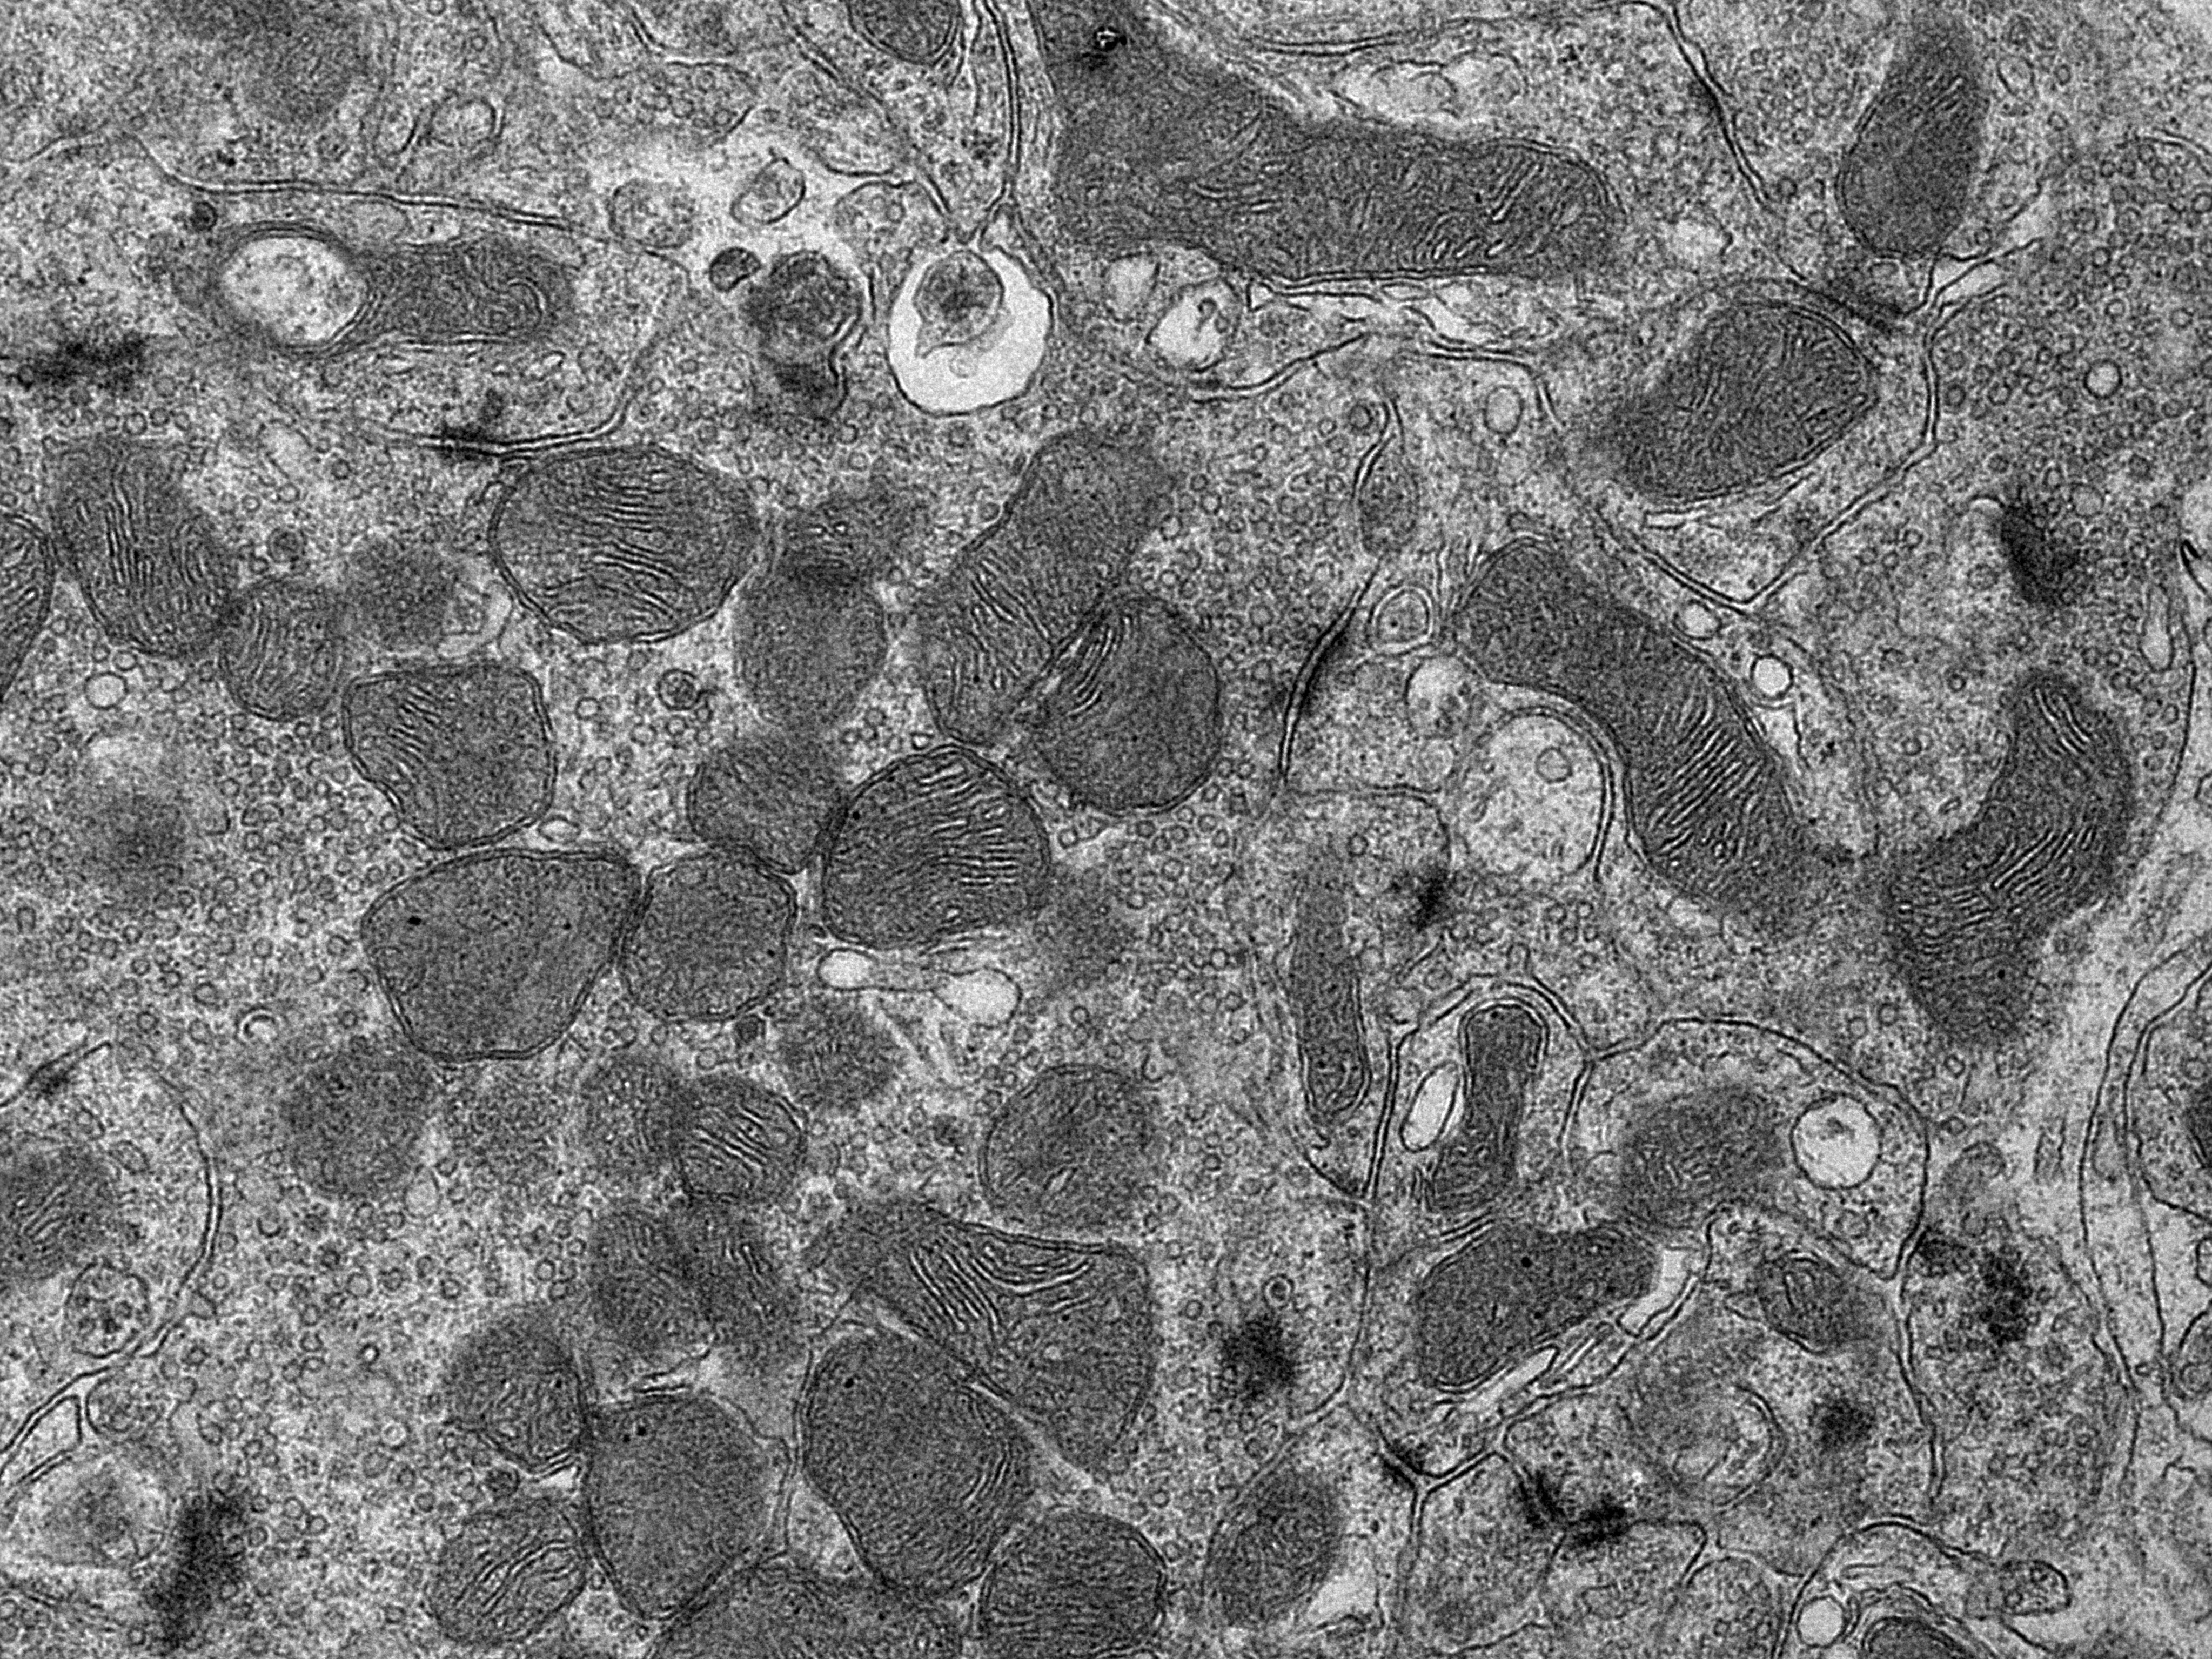

Unser Körper benötigt Energie – für jeden Stoffwechselprozess, jede Bewegung und zum Atmen. Diese Energie wird in winzigen Bestandteilen unserer Körperzellen hergestellt, den sogenannten Mitochondrien. Im Gegensatz zu anderen Zellbestandteilen besitzen Mitochondrien ein eigenes Erbgut, die mitochondriale DNA. In bestimmten Situationen geben Mitochondrien ihre DNA jedoch in das Zellinnere ab, was eine Reaktion des zelleigenen Immunsystems hervorruft und mit diversen Krankheiten und dem Alterungsprozess in Verbindung gebracht wird. Die Gründe für die Freisetzung der mitochondrialen DNA sind bislang nicht bekannt.

Um die Frage zu beantworten, wann Mitochondrien ihre DNA abgeben, haben sich Forschende am Max-Planck-Institut für Biologie des Alterns auf das mitochondriale Protein YME1L konzentriert, das seinen Namen Hefemutanten verdankt, die ihre mitochondriale DNA freisetzen – yeast mitochondrial escape 1. „In Zellen ohne YME1L, haben wir die Abgabe der mitochondrialen DNA in das Zellinnere und eine damit zusammenhängende Immunreaktion in den Zellen beobachtet“, sagt Thomas MacVicar, einer der beiden Erstautoren der Studie. Bei genaueren Untersuchungen wurde ein direkter Zusammenhang zu den Bausteinen der DNA festgestellt. „Fehlt den Zellen YME1L, kommt es zu einem Mangel an DNA-Bausteinen im Zellinneren“, schildert Thomas MacVicar. „Dieser Mangel löst die Freisetzung der mitochondrialen DNA aus, was wiederum eine Entzündungsreaktion in der Zelle hervorruft: die Zelle löst ähnliche Entzündungsreaktionen aus wie bei einer bakteriellen oder viralen Infektion. Geben wir den Zellen DNA-Bausteine von außen hinzu, stoppt das auch die Entzündung.“